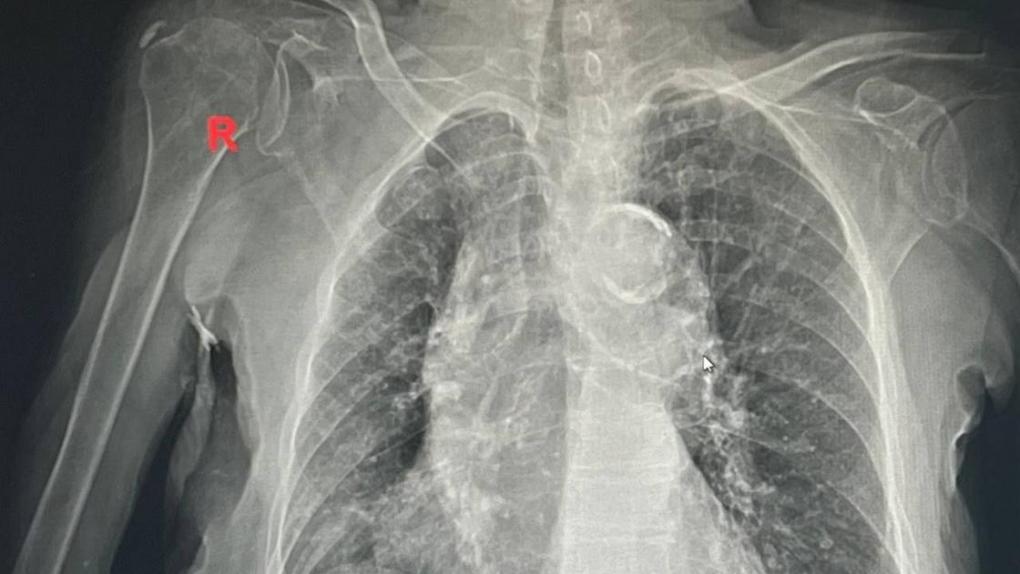

У бабушки обострился хронический бронхит. Фото: Снимок предоставлен заведующим пульмонологическим отделением ГКБ №1 Эдуардом Капраловым

Пару недель назад в  ГКБ №1 имени Кабанова поступила 100-летняя бабушка с  обострением хронического бронхита лёгких, рассказали в  Минздраве Омской области. Женщина болела в  течение пяти дней и  в  один момент почувствовала, что  ей стало хуже  — у  неё поднялась температура до  40  градусов. После этого муж правнучки вызвал скорую и  привёз бабушку в  больницу.

В  течение четырёх дней медики делали всё, чтобы ей помочь. И  им удалось  — омичку выписали домой в  удовлетворительной состоянии. Врачи передали бабушку в  руки родственников для  долгожданной встречи с  праправнуком.